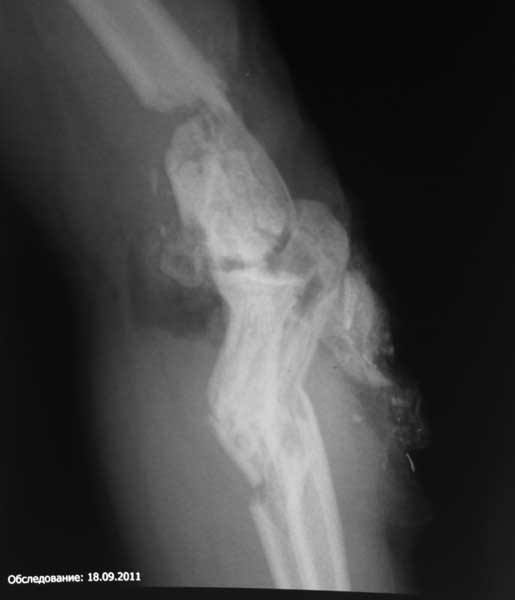

Re: тяжёлое повреждение локтевого сустава

Прошу простить за задержку - не было линии. Шлю снимки.